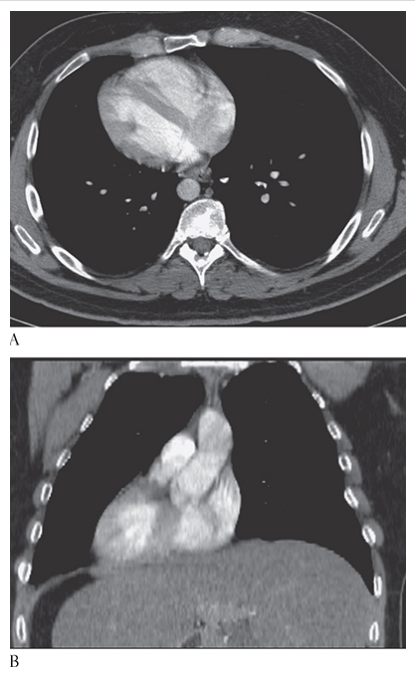

Atrial Myxoma. Contrast-enhanced axial CT shows a round filling defect/mass in the left atrium consistent with a myxoma (arrow).

Atrial Myxoma. Contrast-enhanced coronal MPR CT shows a round filling defect/mass in the left atrium consistent with a myxoma (arrow).